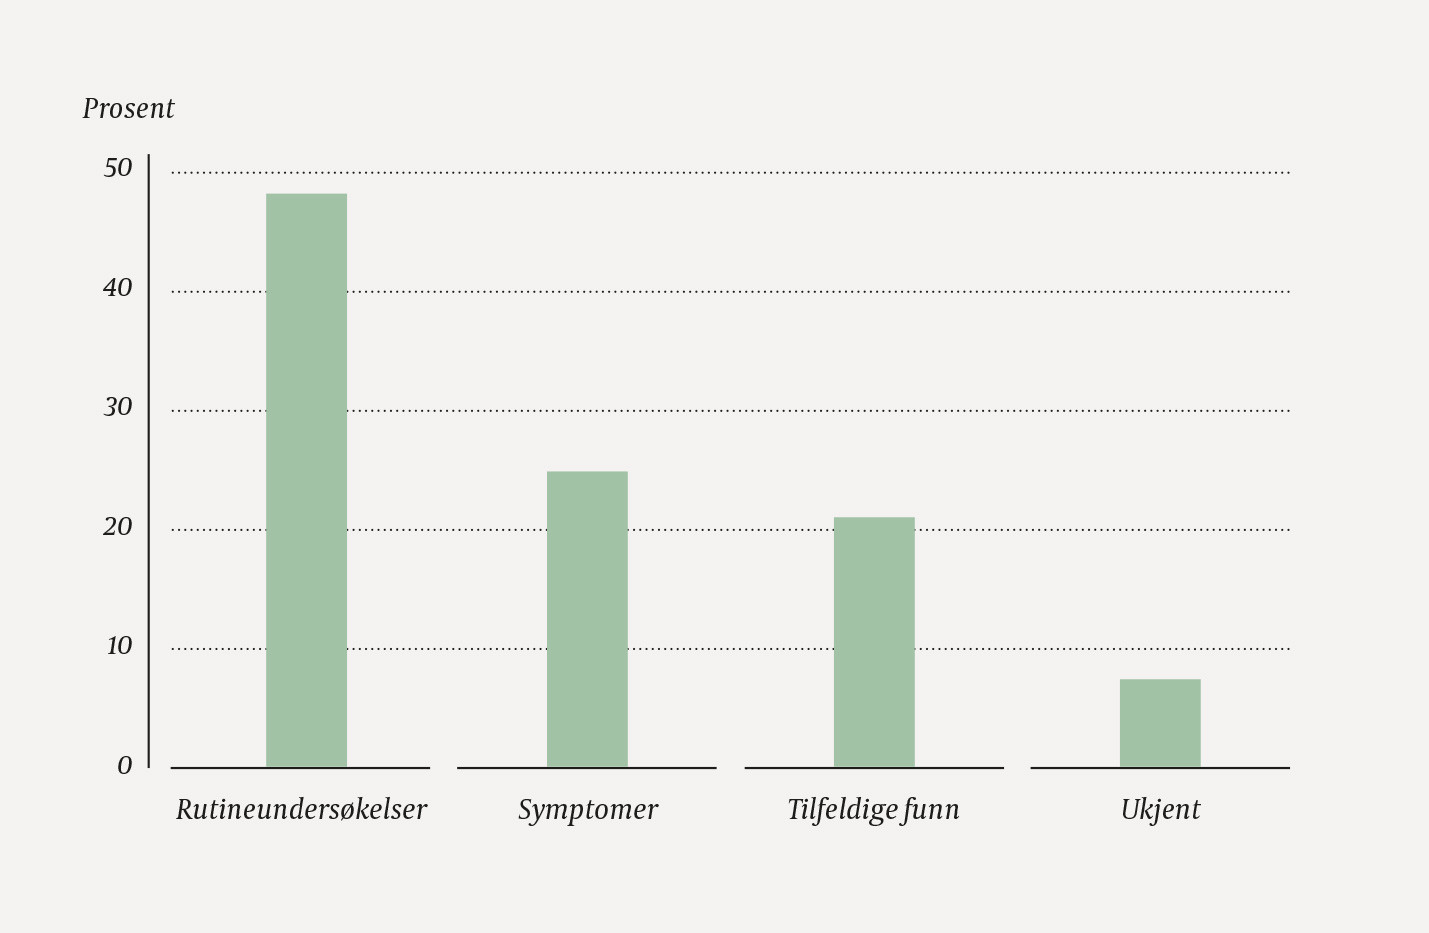

Diagnosetidspunkt ved de ulike hjertefeilene hos de levendefødte barna er presentert i tabell 2. Hos 73 av 130 (56 %) barn ble diagnosen stilt etter fødsel, og blant disse ble diagnosen stilt etter utskrivning fra sykehus hos ni (12 %) barn. Årsakene til at hjertefeilen ble oppdaget etter fødsel er presentert i figur 1. Hos 35 av de 73 (48 %) barna ble hjertefeilen oppdaget ved rutineundersøkelser. Av disse ble 16 (46 %) barn identifisert ved legeundersøkelse før utskrivning fra barselavdeling. Vanligste kliniske funn som indikerte hjertefeil ved denne legeundersøkelsen var bilyd (15 av 16 (94 %) barn) ved auskultasjon over hjertet. Hos 11 av 35 barn hvor hjertefeilen ble oppdaget ved rutineundersøkelse etter fødsel, skjedde dette som følge av pulsoksymetriundersøkelse. Færre enn fem barn født i 2016 fikk hjertefeildiagnose i forbindelse med oppfølging på helsestasjonen. Hovedårsaken hos alle som ble henvist derfra, var bilyd over hjertet.

Denne studien av påvisning av alvorlige medfødte hjertefeil i Norge i 2016 viste at 58 % av hjertefeilene ble oppdaget før fødsel. Hos 48 % av barna med postnatal diagnose ble hjertefeilen oppdaget på grunn av rutineundersøkelser. Hos 12 % av de levendefødte barna uten kjent hjertefeil ble tilstanden oppdaget først etter utskrivning fra sykehuset. Koarktasjon av aorta var vanligste diagnose ved sent oppdaget hjertefeil.

Oppsummert viser denne studien at de fleste barn med alvorlige medfødte hjertefeil oppdages ved ultralydundersøkelse i svangerskapet eller ved rutineundersøkelser før utskrivning fra barseloppholdet. Blant barn som fikk påvist alvorlig hjertefeil etter fødselen, ble likevel nesten halvparten oppdaget utenom rutinemessige undersøkelser, på grunn av symptomer eller som tilfeldige funn. Hos noen barn, særlig ved koarktasjon av aorta, erkjennes imidlertid ikke diagnosen før etter utskrivning fra sykehus etter barseloppholdet. Vi vil understreke viktigheten av umiddelbar sykehusinnleggelse og rask vurdering av barnekardiolog av små barn med mistanke om alvorlig hjertefeil. Denne studien viser også at det er behov for løpende kvalitetssikring av metodene for å oppdage hjertefeil. Å etablere et nasjonalt kvalitetsregister over medfødte hjertefeil vil være et viktig verktøy i det arbeidet.